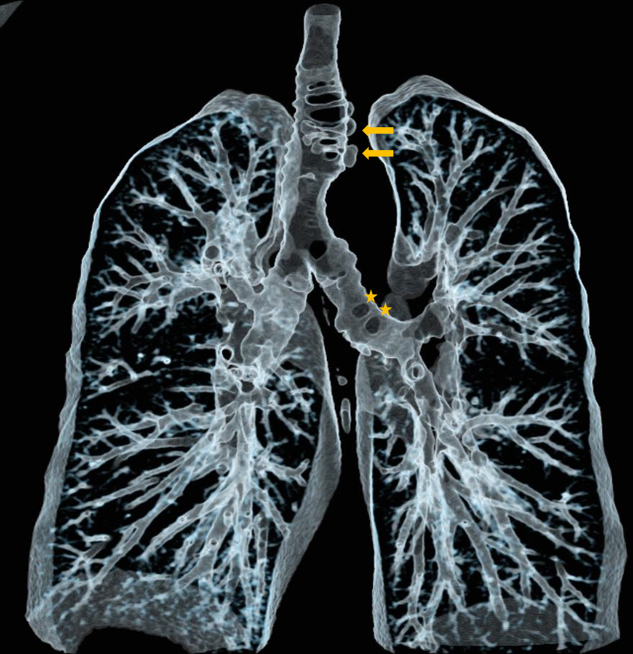

教学要点气管憩室病是一种罕见的良性疾病,其特征是单个或多个气管壁外袋,可以是先天性的,也可以是后天性的,通常在胸部高分辨率计算机断层扫描中偶然被诊断出来,一般情况下没有任何症状。

Teaching point: Tracheal diverticulosis is a rare and benign disorder, characterized by single or multiple tracheal wall outpouchings, either congenital or acquired, usually diagnosed incidentally on chest high‑resolution computed tomography, and in general remaining asymptomatic.